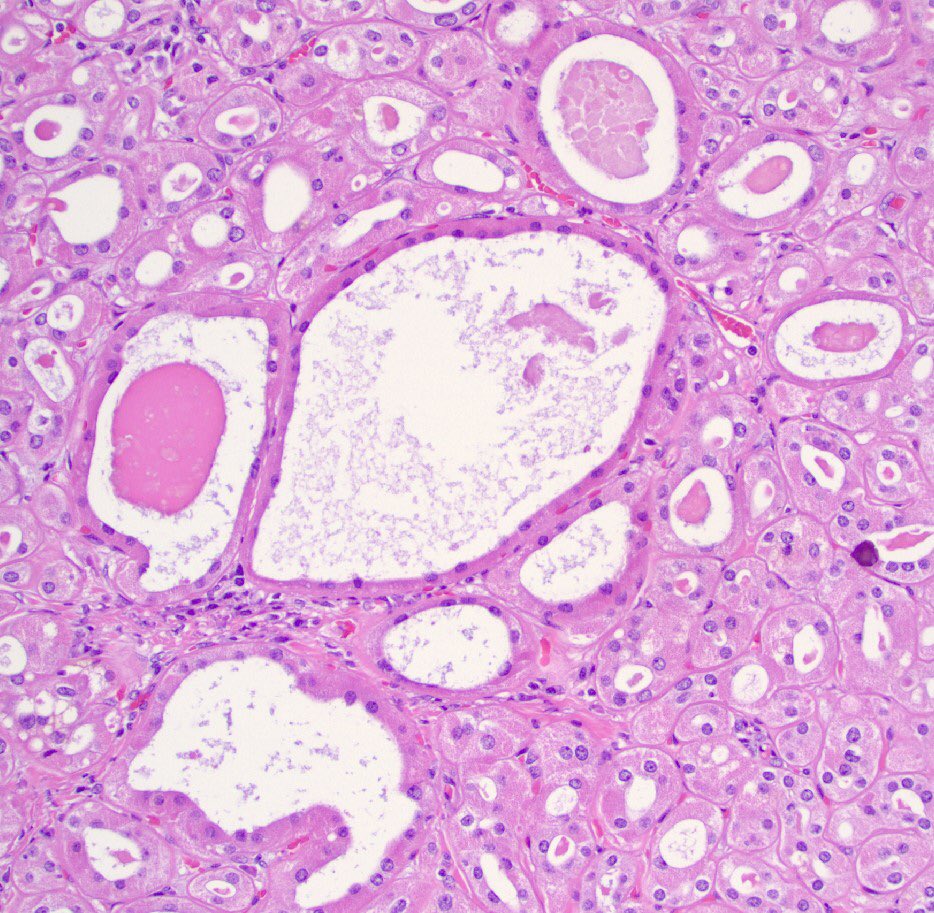

4.3 cm renal mass confined to kidney, tumor cells are predominantly with proliferative, tubular pattern 🎨 CK7 positive (strong, diffuse) 🎨 CD117 negative Thoughts? Sean R Williamson MD Kiril_T_Can Michelle_Hirsch (Donovan) Priya Rao, MD Ankur Sangoi

Kidney, young F adult #gupath Dr. Luca Olaleke Folaranmi Aurélien Morini, MD, MSc 🇫🇷🇪🇺💙💛 Celina Stayerman MD 🔻Nusrat Zahra🔻🇵🇸 @miss_me1986 Gonzalo De Toro Tristan Rutland MBBS FRCPA IFCAP Anandi Lobo, MD Sumanta Das Lorand Kis Erik Kouba bansar Carlos Miguel Ruiz Carlos Nieves Padma Priya J Susan Prendeville @AkgulMd Ankur Sangoi Barry McGinn